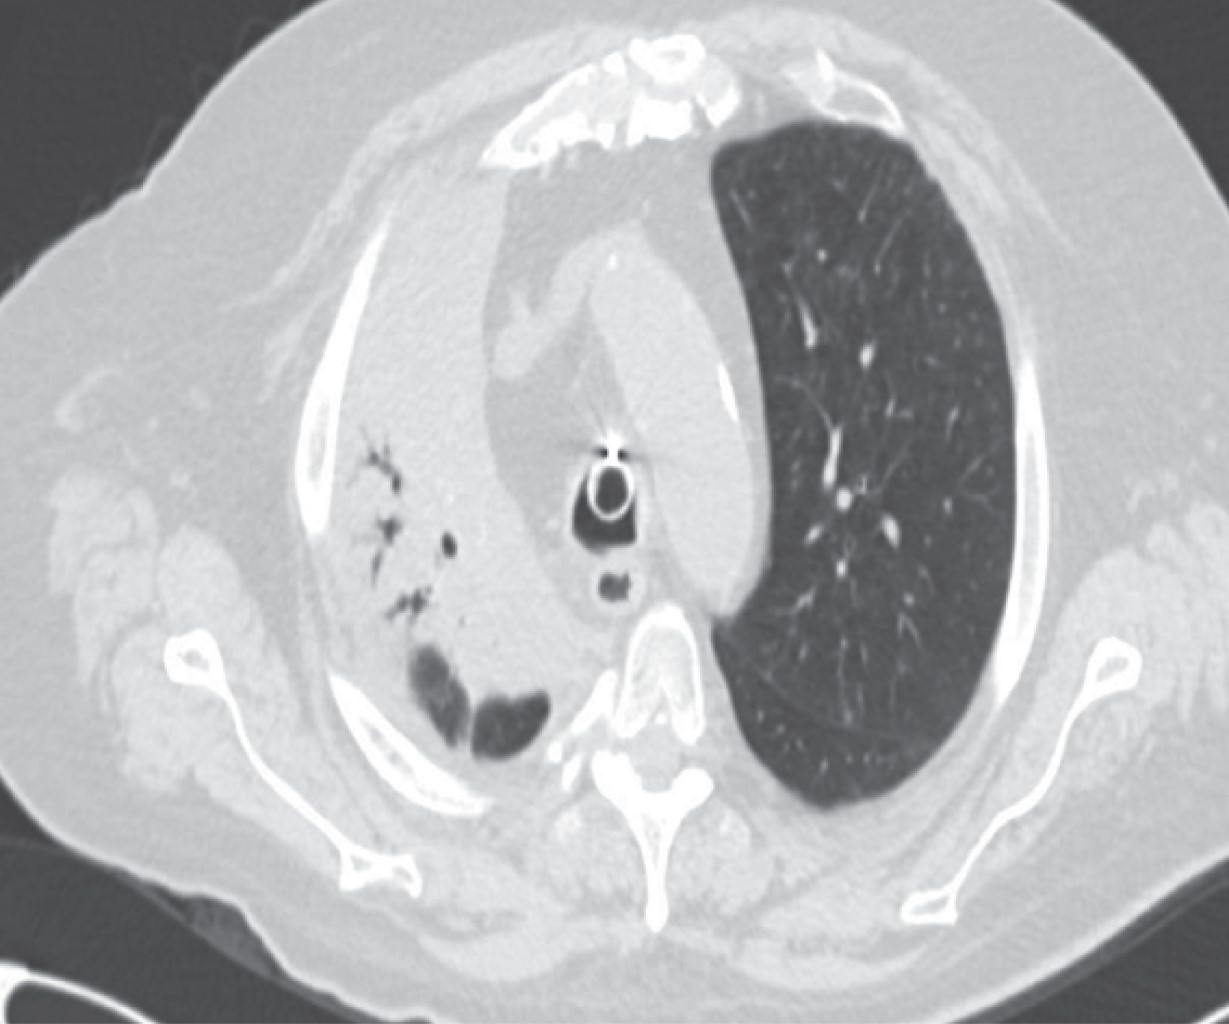

The appearance of a multiple primary malignant neoplasms is more frequent in elderly patients, lung cancer is the leading cause of cancer death worldwide, the frequency of synchronous and metachronous lung cancers has increased in recent years due to advances in early detection techniques, multiple malignancies can be classified as synchronous or metachronous according to the time of onset in relation to the first malignancie, synchronous those that appear in the first six months and metachronous as those that appear after six months. We present the case of a 66-year-old male patient with a history of right radical nephrectomy for clear cell renal cancer, who goes to the emergency department seven years later for respiratory symptoms and hemoptysis. In his study protocol, he is diagnosed with a parahiliary right upper lobe endobronchial tumor of epidermoid lineage involving the right bronchus.

Figure 4